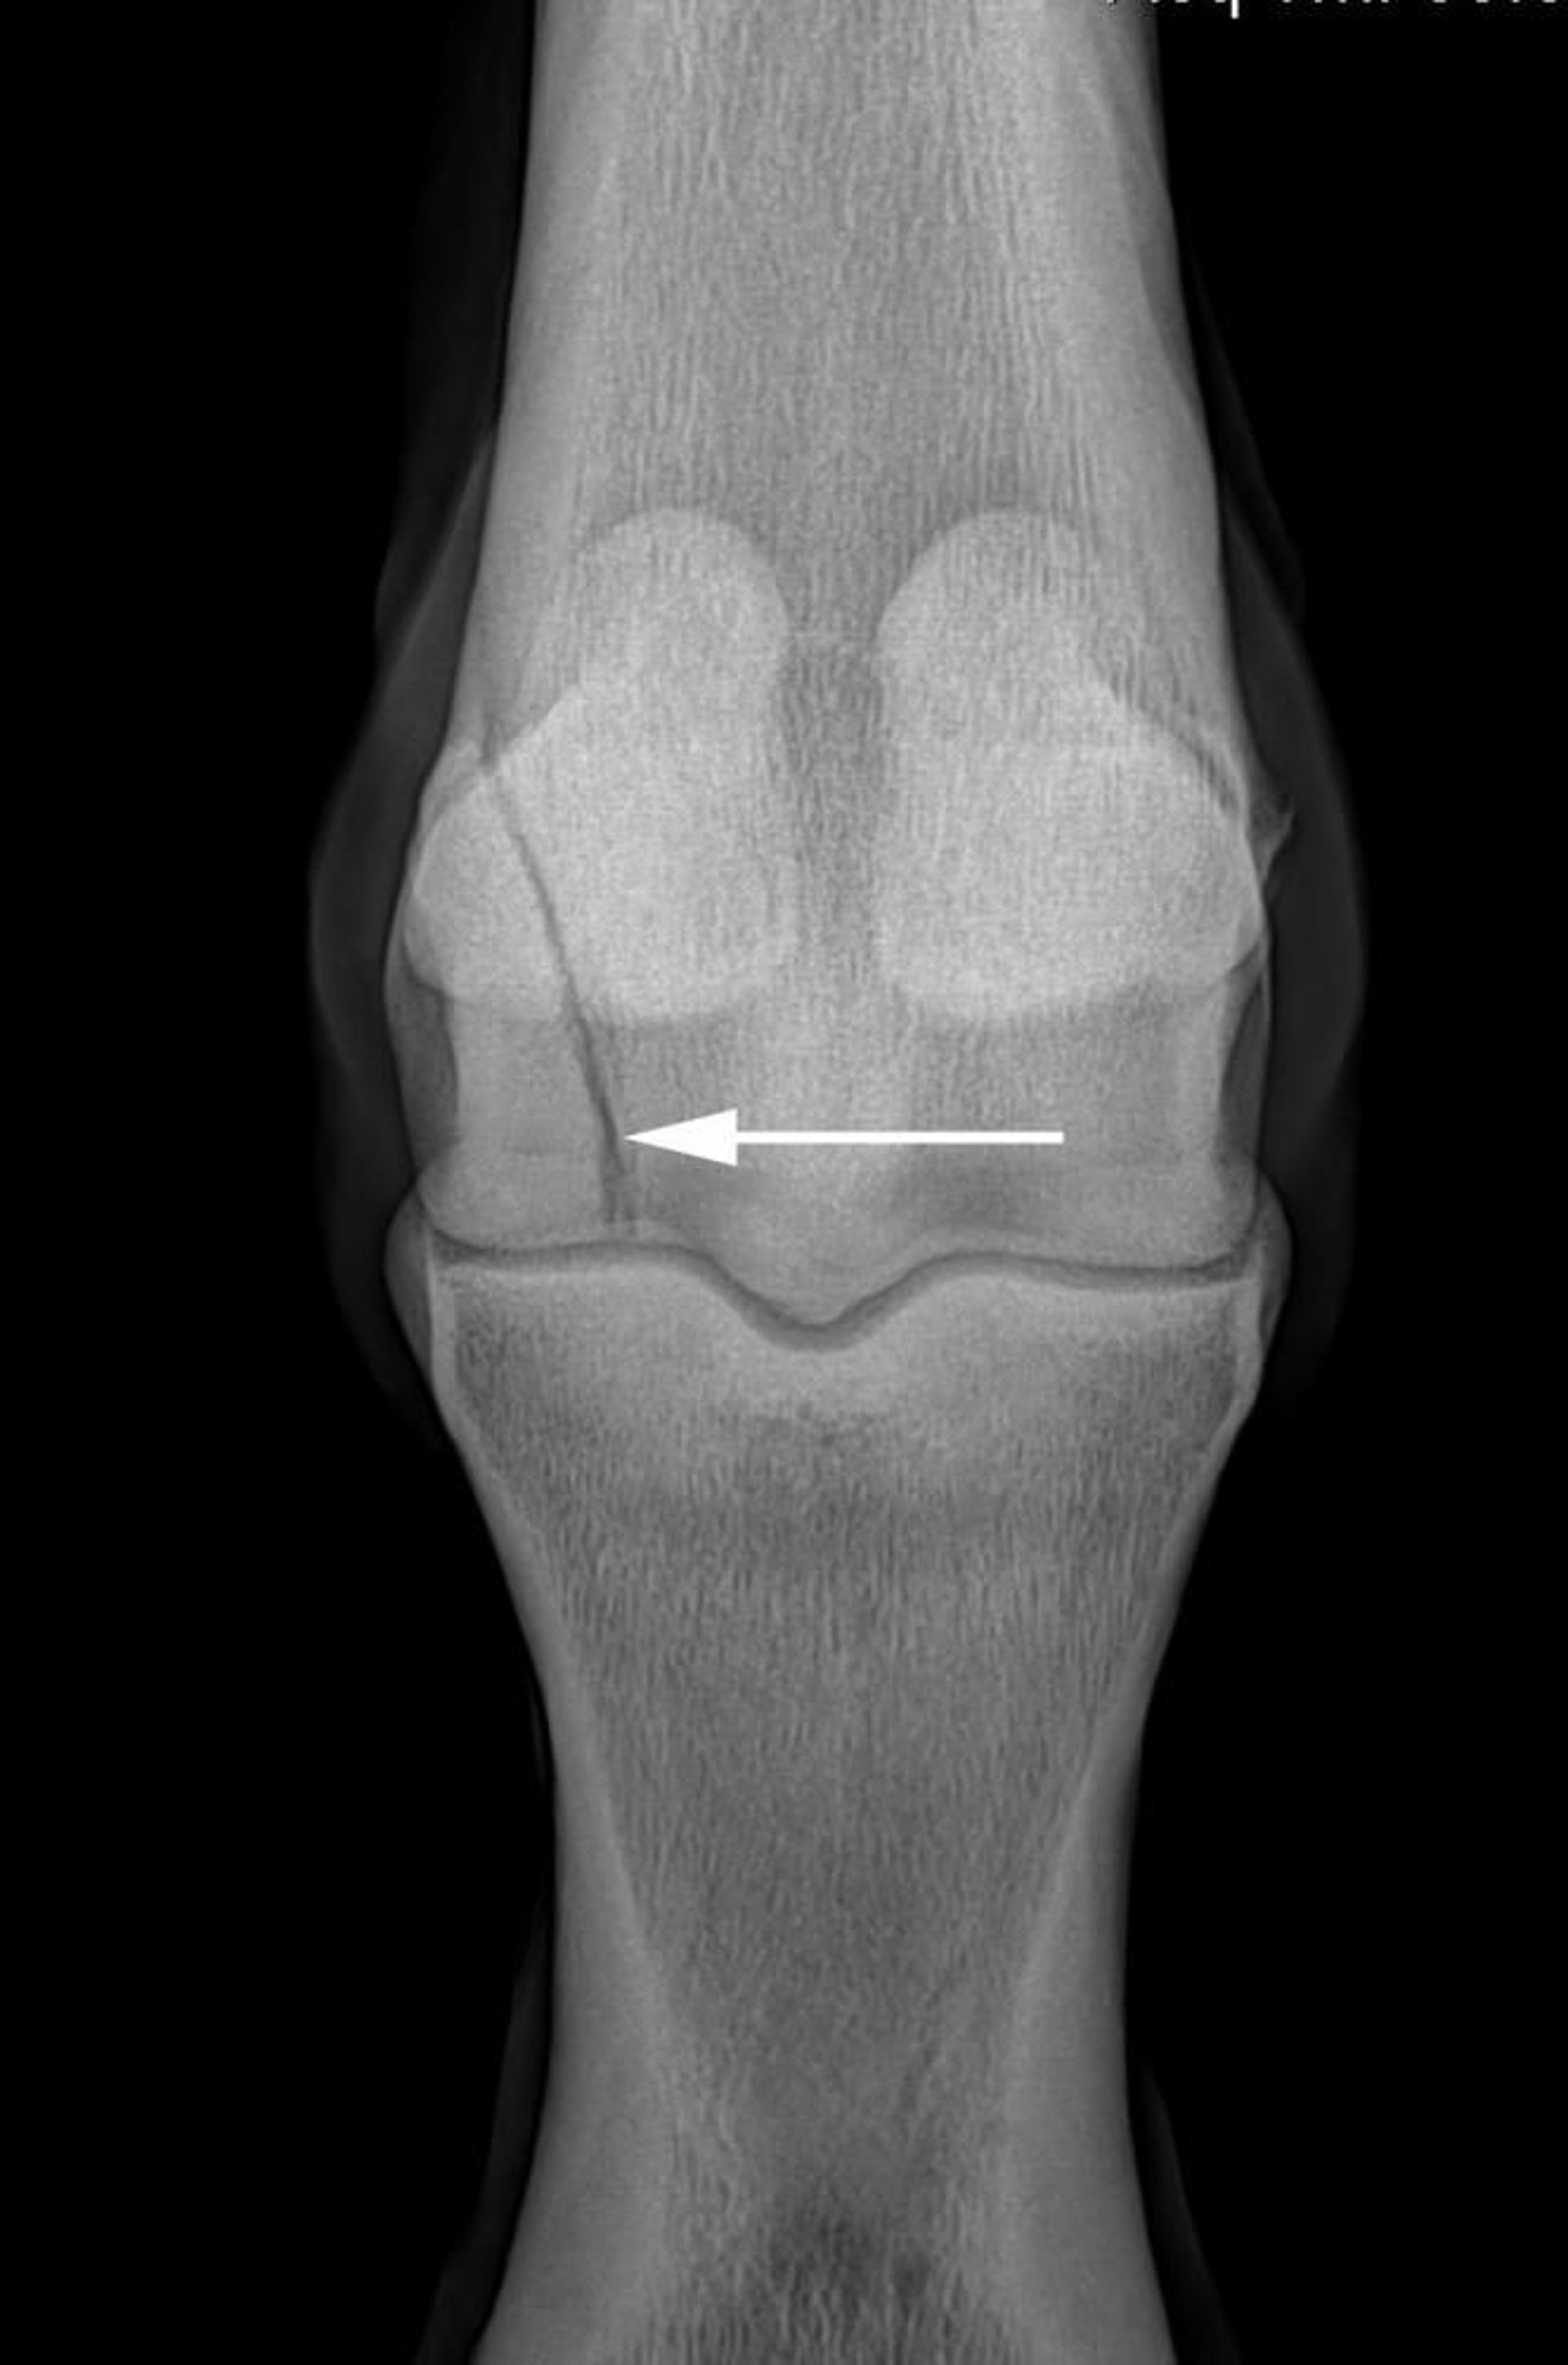

Elevated dorsopalmar radiograph showing a lateral condylar fracture (arrow) of the distal third metacarpal bone in a horse.

Courtesy of Dr. Matthew T. Brokken.